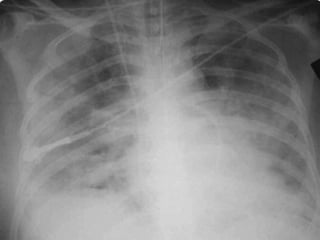

• “Lesão pulmonar inflamatória aguda e difusa,

hipoxemia e opacidades radiográficas bilaterais,

▫ Infiltrado bilateral

▫ POAP < 18 mmHg

DEFINIÇÕES DE BERLIM

• Tempo de inicio agudo:

▫ Dentro de uma semana após uma injúria

conhecida ou nova ou piora respiratória

• Raio X do tórax:

▫ Opacidades bilaterais não explicáveis por efusões,

atelectasias ou nódulos